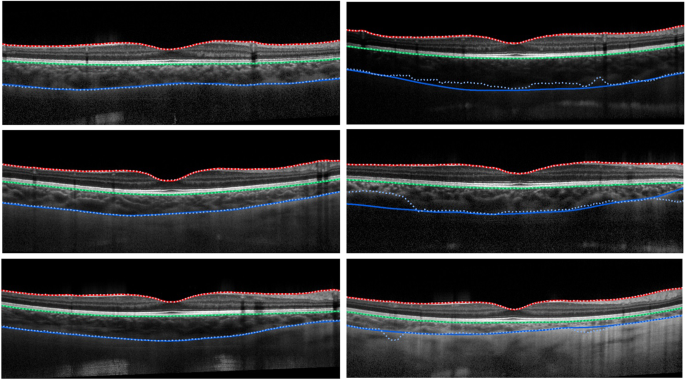

Each of the semantic segmentation networks depicted in Fig. 2 were trained and evaluated as described in the Methods section. Like the patch-based methods, all networks were trained and evaluated using contrast-enhanced images in addition to the raw images. Results for the dice overlap are presented in Supplementary Table S5 while the boundary position errors are reported in Table 2. Using the mean absolute boundary errors, a repeated measures ANOVA was performed to examine the statistical significance of any differences in performance between the methods. Figure 5 presents some example segmentations using the standard U-net architecture (without contrast enhancement). The networks converged in an average of 77.57 ± 18.46 epochs with a range of 34–98 epochs.

Example segmentations for the standard U-Net architecture (no contrast enhancement). Solid lines correspond to the true boundary positions and the dotted lines represent the predicted locations. Left: three cases of successful delineation of all boundaries with close agreement between the predictions and truths. Right: three cases of failure on the CSI boundary with observable differences between the prediction and truth.